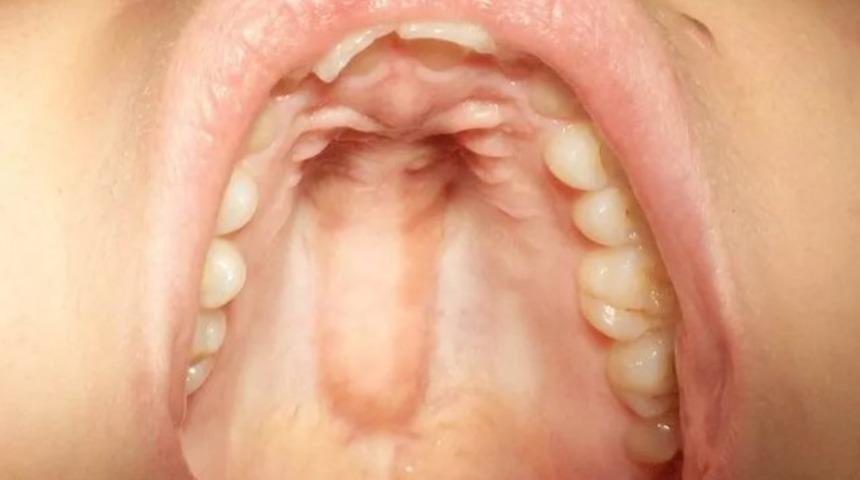

Dilinizi damağınızın üzerinde gezdirin; düz mü hissediyorsunuz yoksa hafif bir yumruya mı rastladınız? Dünya genelinde, ağzında bu şişlikle yaşayan insanların belli bir sayıda olduğunu unutmayın! Çoğunlukla kadınlarda görülen bu kütle, semptomsuz bir kemik büyümesidir.

Torus Palatinus olarak adlandırılan bu sert şişliğin bir zararı yok. Damak üzerinde bulunan bu kütlenin boyutu herkeste farklılık gösterir; 0.2-0.6 cm olarak değişir. Ortalama bir sayı vermek gerekirse, dünya nüfusunun %20 ile %30'unda Torus Palatinus var. Kadınlarda bulunma oranı yüksek olan bu kütlenin, araştırmalar sonucunda Asya kökenli kadınlarda daha yaygın olduğu gözlemlenmiştir. Ayrıca bu şişliğin genetik bir hikayesinin de olduğunu gösteren incelemeler de vardır.

Torus Palatinus, ağrısız bir kemik büyümesidir. Herhangi bir ağrı yaşatmayan bu şişlik, farklı şekillerde de görülebilir; düz, nödüler veya iğ ipliği gibi uzundur.

Hızlı büyümediği için birçok insan bu sert şişliğin farkında değildir. Genellikle ergenlik çağında başlama oranı yüksektir ve orta yaş dönemine gelince fark edilmeye başlanır. Torus Palatinus, kemik gibi sert olduğu için yaşlandıkça büyümez; kemik erimesi ile beraber küçülür.